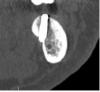

doktorenok Опубликовано 23 июня, 2013 Поделиться Опубликовано 23 июня, 2013 Вот такое язычное поднутрение в позиции 36, 37 5лет как отпротезировано-полет нормальный Ссылка на комментарий

IvanK Опубликовано 23 июня, 2013 Поделиться Опубликовано 23 июня, 2013 5лет как отпротезировано-полет нормальныйПерфо.JPGТам такая картикалка, что не заметить при сверлении не возможно было.. или это нарочно?Какова длина имплантата? Ссылка на комментарий

doktorenok Опубликовано 23 июня, 2013 Поделиться Опубликовано 23 июня, 2013 Там такая картикалка, что не заметить при сверлении не возможно было.. или это нарочно?Какова длина имплантата? Самая первая работа, длину не помню. Ссылка на комментарий